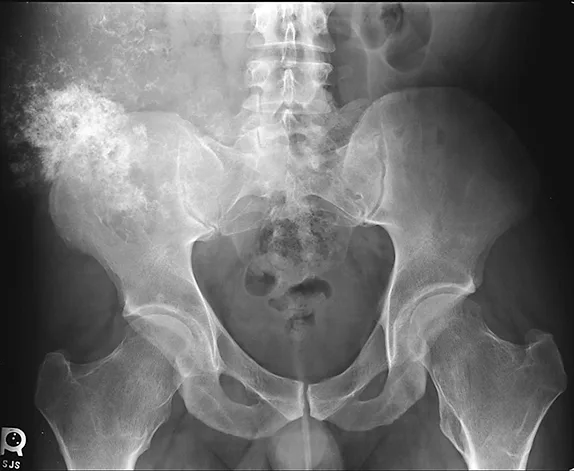

FIGURE 1

Anteroposterior radiograph showing a large mineralized mass with poorly defined margins and a wide zone of transition arising from the right ilium

DIAGNOSIS

Previously obtained anteroposterior pelvic radiographs (Figure 1) showed a large, poorly defined, mineralized lesion involving the right ilium. Because of the patients physical examination results, history of MHE, and radiographic findings, a secondary chondrosarcoma of the right ilium was suspected. Further diagnostic evaluation, including a CT scan (Figure 2) and MRI of the pelvis, were obtained to further characterize the lesion and begin surgical planning.